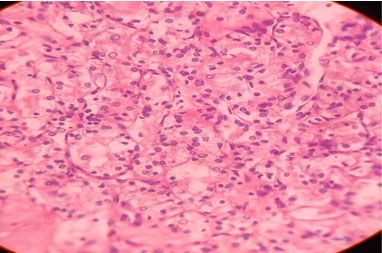

Figure 4: Histopathology picture showing RCC.

Share Image: